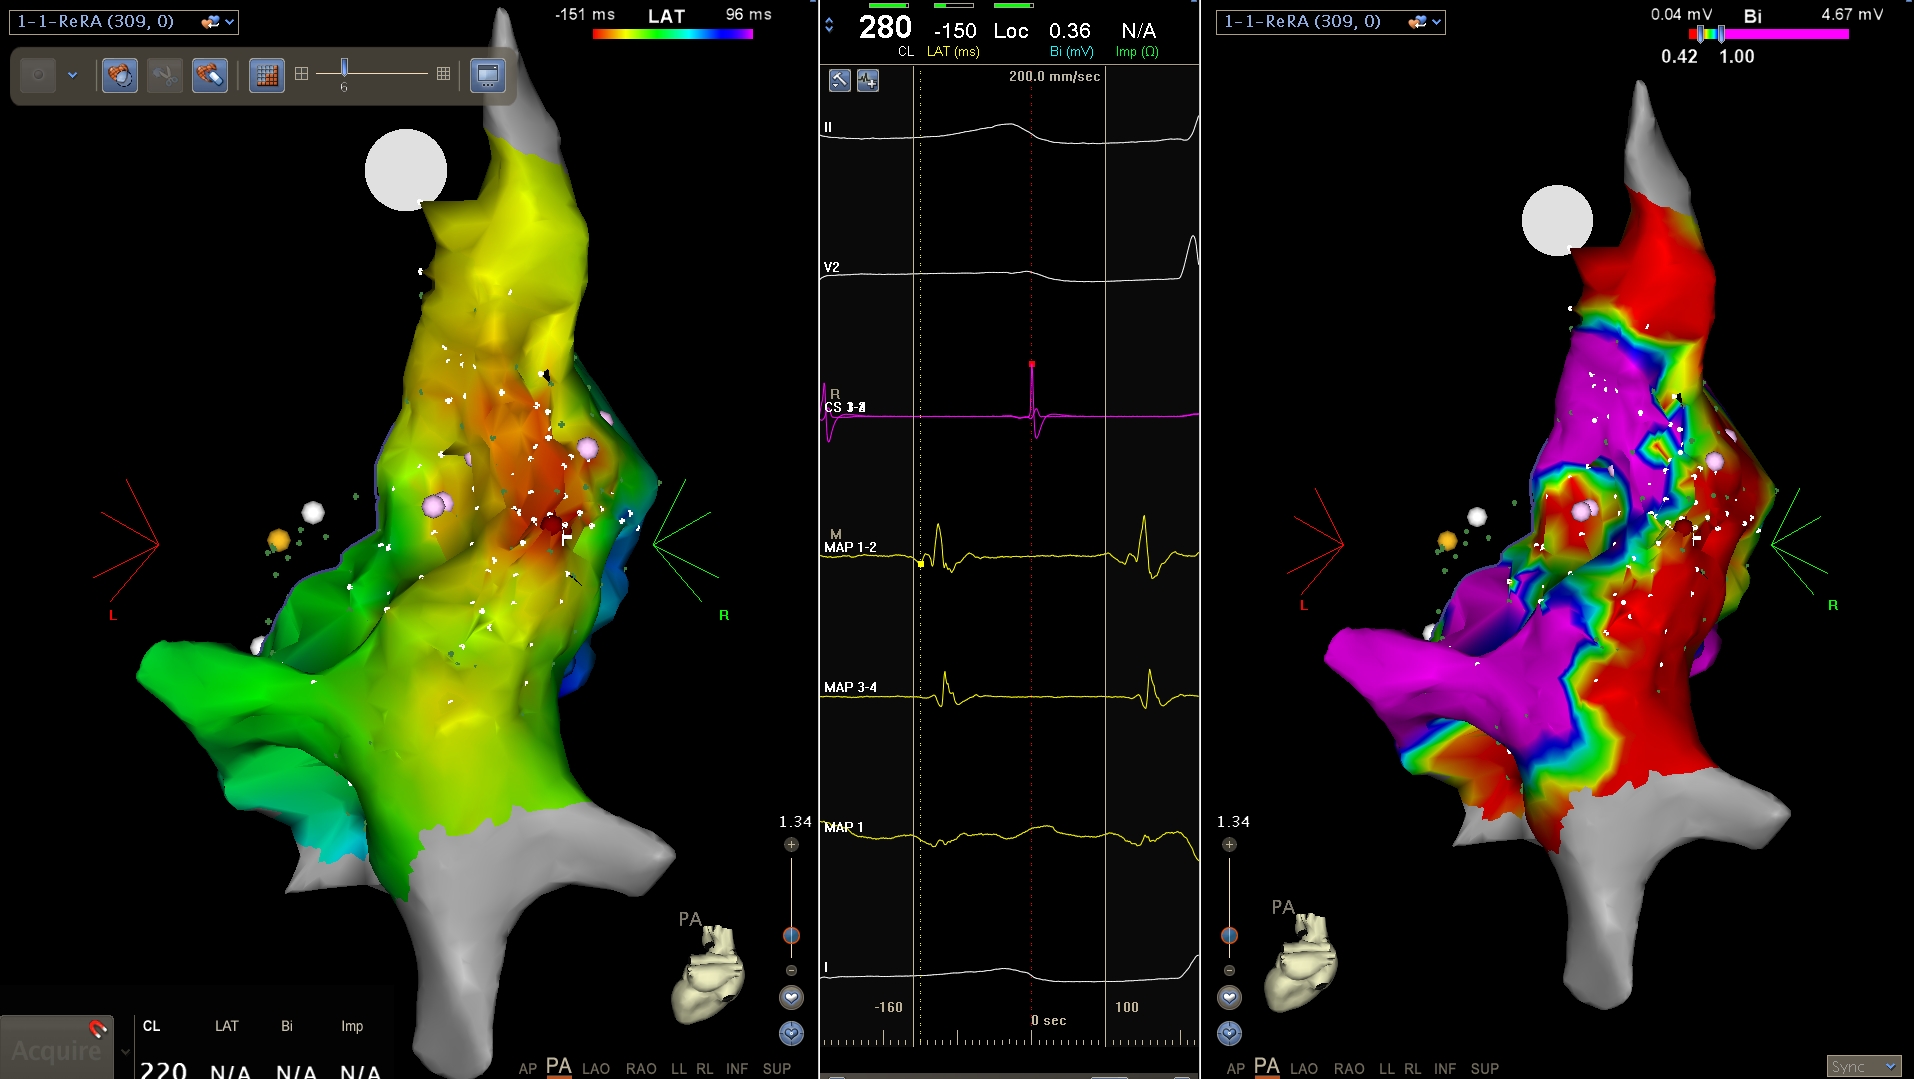

Activation map

• Isochronal map

• Activation time in relation to fixed reference

• Similar activation times marked with same colour